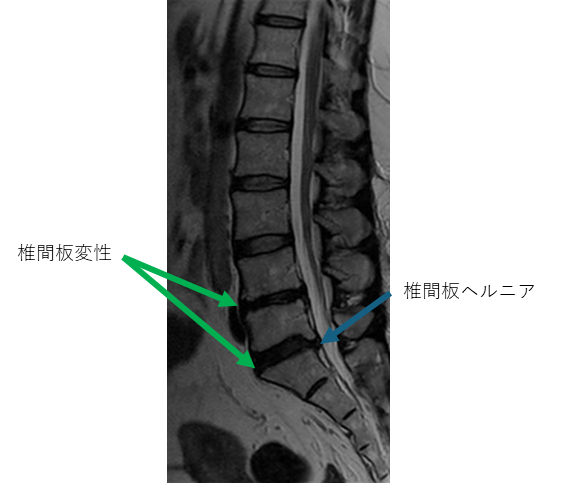

画像及び所見について

L1/2: 異常なし

L2/3: 異常なし

L3/4: 異常なし

L4/5: 椎間板変性

L5/S: 椎間板変性、椎間板ヘルニア

以上の事が画像上認められます。

4/5,5/s に

椎間板変性、椎間板ヘルニアを認め、主症状の原因の可能性が高い。